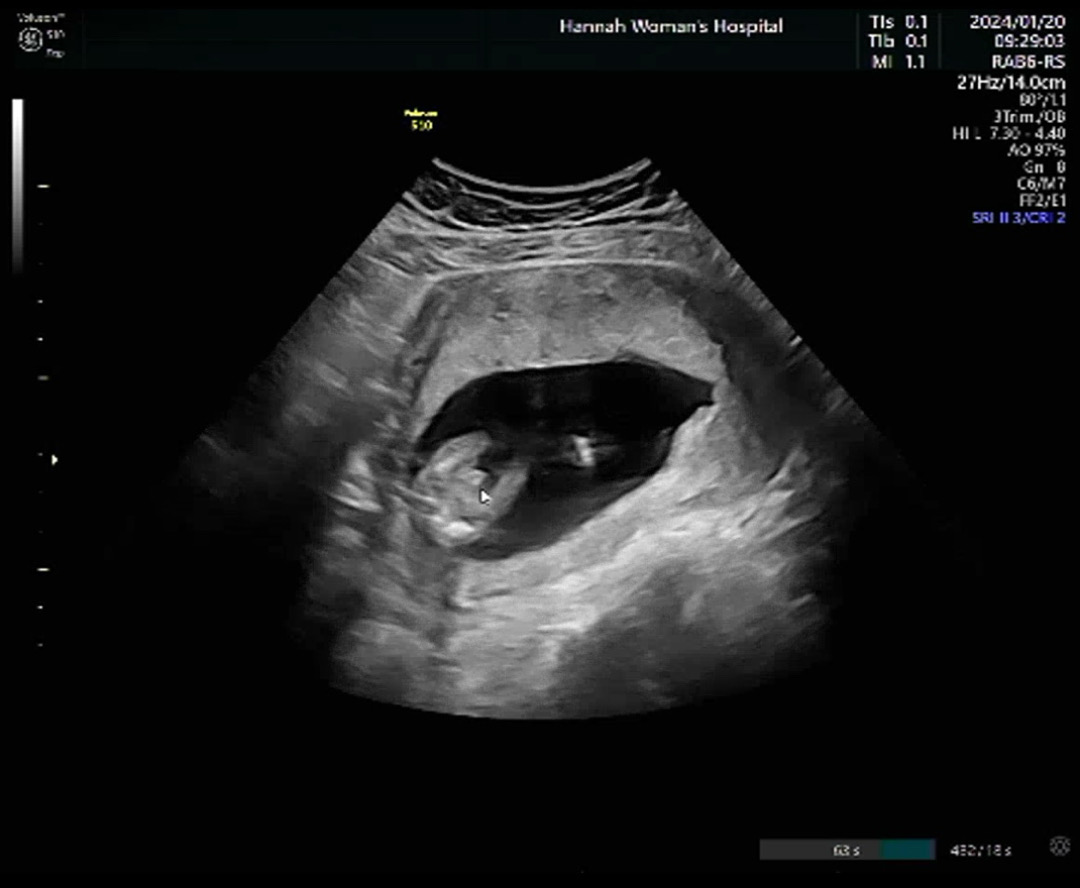

15주1일차 촘파 봐주세요!!

아들맘 확정인거죠?!! 🌶️존재감이 뿜뿜하네요ㅋㅋㅋㅋㅋ 의사쌤도 튀어나온거 보이나면서ㅋㅋㅋ 다들 보시기에 어떠신가요? 댓글 남겨주세요😊😊

그쵸!! 아들맘 확정이요~~😊